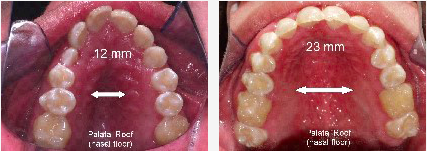

Narrow Palate = Narrow Airway , Wide Palate = Airway Expanded

Babies typically exhibit 'perfect' facial structures with forward growth, a result of natural nose breathing. Tongue pressure on the palate during childhood supports forward maxilla growth, shaping the face and teeth alignment. Adults with improper oral posture often have narrow, 'V'-shaped palates, leading to crowded teeth and other issues. Childhood habits significantly influence maxilla development.